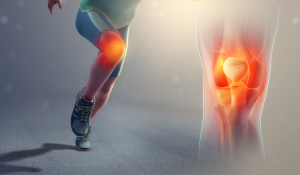

Що таке гонартроз?

Гонартроз – це ураження колінного суглоба, яке відбувається внаслідок руйнування колінного хряща та подальших змін його структури. До даного захворювання найбільш схильні жінки в похилому віці.